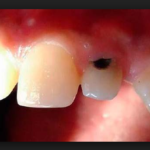

Кариес корня зуба фото

Кариес на корне зуба визуально практически никогда не определяется. Очень редко, и лишь в случаях, когда зубной камень значительно опустил ткани десны, может быть видно темное пятно или изъязвленный участок эмали. Чаще всего кариесом развивается на корнях передних нижних зубов и в межзубном промежутке. Во втором случае можно заметить снижение высоты десневого сосочка и увеличение межзубного промежутка в самой нижней его части.